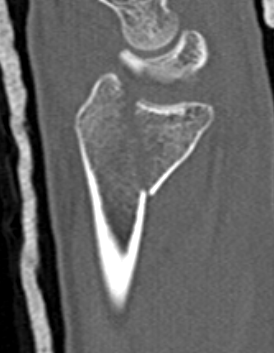

Distal Radius Angles

- radial volar tilt 11°

- radial inclination 22°

- radius is 11 mm longer than ulna

- ulna variance 2mm positive on average